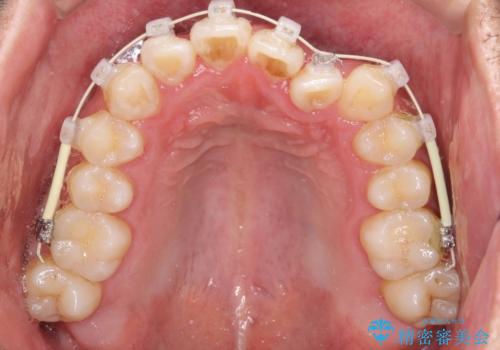

前歯が反対にかんでいる インビザラインとワイヤーを組み合わせた矯正治療

- 前歯が正常とは反対にかんでいるとのことで、来院されました。

患者様がマウスピースを希望されていましたが、上の前歯のがたつきを先にワイヤーで改善する方が早く治療が終了することが可能であるとお伝えし、上顎のみ半年間ワイヤーで治療を行いました。